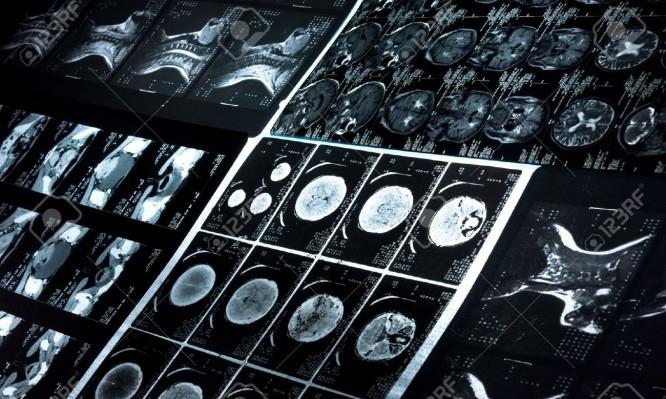

Tο νέο Κέντρο Ερευνών Απεικόνισης του Εγκεφάλου του Πανεπιστημίου του Cardiff (Cardiff University Brain Research Imaging Research) στοχεύει να γίνει ένα από τα κορυφαία ερευνητικά κέντρα για νευροαπεικονίσεις στην Ευρώπη. Το κέντρο φιλοξενεί τέσσερα συστήματα MRI (μαγνητικής τομογραφίας) που θα βοηθήσουν ώστε να αποκαλυφθούν ζωτικής σημασίας στοιχεία για την ανάπτυξη καλύτερων νευρολογικών και ψυχιατρικών θεραπειών, για ασθένειες όπως είναι η Σκλήρυνση κατά Πλάκας και η σχιζοφρένεια.

Η έρευνα για τον ανθρώπινο εγκέφαλο που θα πραγματοποιηθεί στο CUBRIC θα χρησιμοποιήσει μεθόδους τεχνολογίας αιχμής που αφορούν απεικονίσεις και γνωστικές τεχνικές, όπως η απεικόνιση μικροδομής, η λειτουργική μαγνητική τομογραφία και η διέγερση του εγκεφάλου. Στη συνέχεια οι μέθοδοι αυτοί θα εφαρμοστούν σε βασικές ψυχολογικές και κλινικές ερωτήσεις. Και τελικά οι επιστήμονες ευελπιστούν ότι η έρευνα θα έχει άμεσο αντίκτυπο στην κατανόηση των νευρολογικών και ψυχιατρικών παθήσεων, συμπεριλαμβανομένων των μεταβολών στον εγκέφαλο που οδηγούν σε διαταραγμένη γνωστική και ψυχική υγεία.

Το Κέντρο και η τεχνολογία της της Siemens Healthineers στοχεύει στο να παρέχει άγνωστες μέχρι σήμερα πληροφορίες σχετικά με τα αίτια των νευρολογικών και ψυχιατρικών παθήσεων όπως η άνοια, η σχιζοφρένεια και η σκλήρυνση κατά πλάκας, καθώς επίσης και την κατανόηση των μηχανισμών ενός υγιούς εγκεφάλου.

Ένα από τα τέσσερα συστήματα MRI που θα χρησιμοποιηθούν επιτόπου, το Magnetom Skyra Connectom 3T1, είναι αυτή τη στιγμή το μοναδικό στο είδος του στην Ευρώπη. Η προηγμένη τεχνολογία του θα επιτρέψει στους επιστήμονες να μελετήσουν τις δομές στο φάσμα micron (δηλαδή στο χιλιοστό του χιλιοστού). Διαθέτει βαθμιδωτά πηνία 300 mT/m που είναι 6 φορές ισχυρότερα από τα αντίστοιχα των συμβατικών συστημάτων MR. Αυτό θα επιτρέψει στους ερευνητές να εξετάσουν τη μικροδομή των ιστών με πολύ μεγαλύτερη λεπτομέρεια και σε περαιτέρω βάθος.